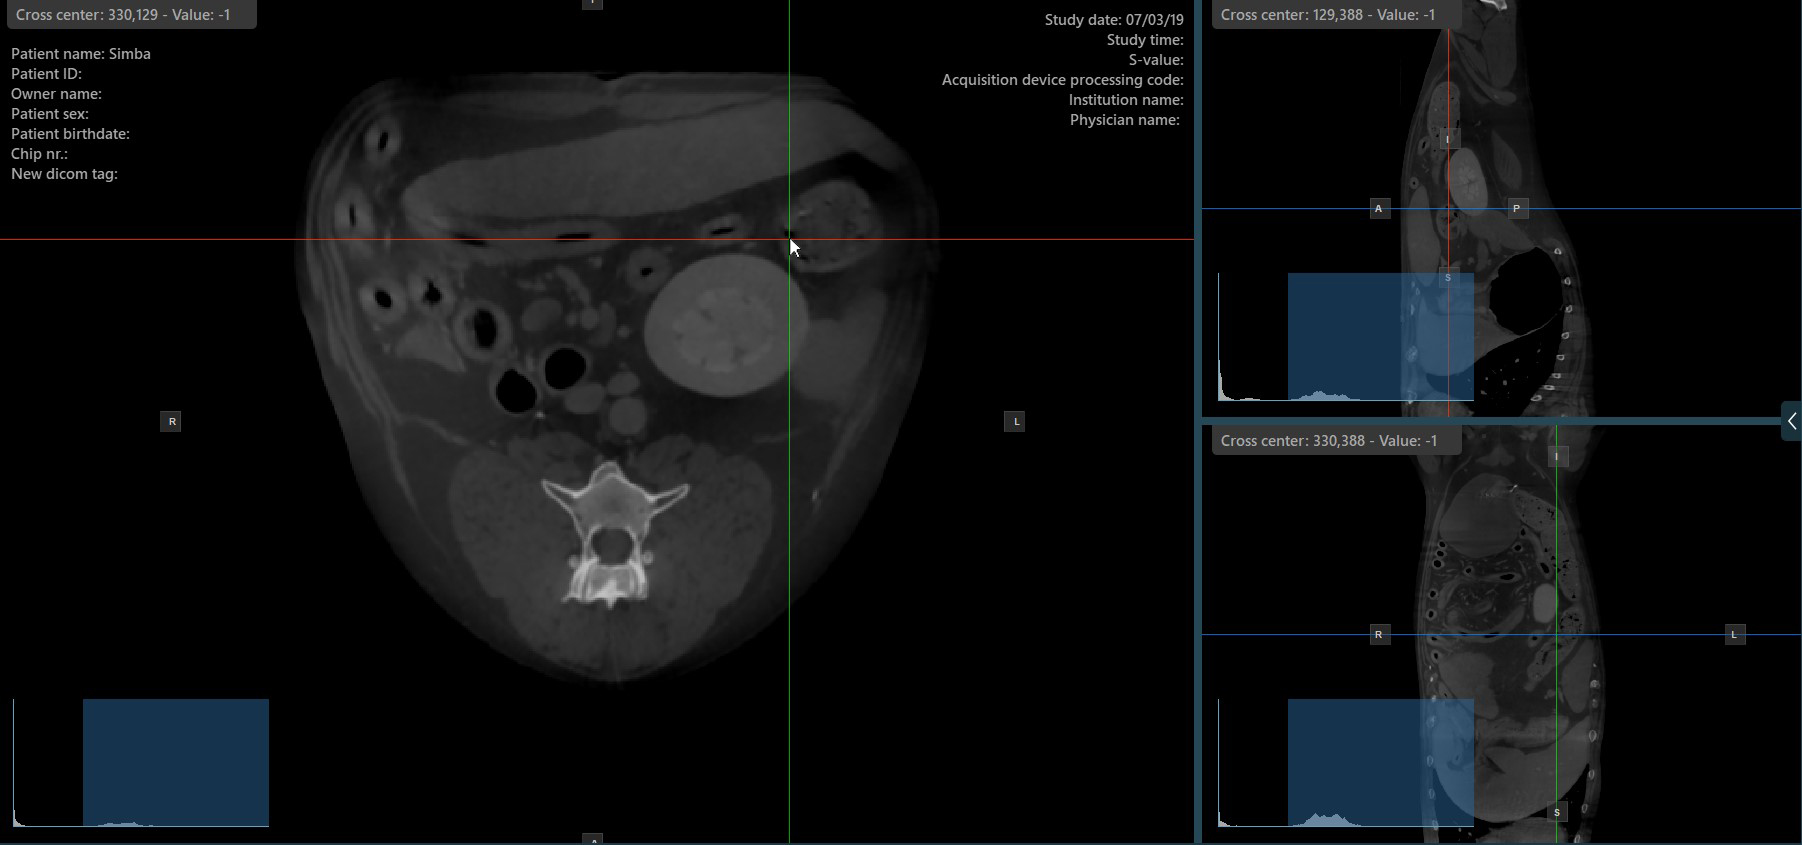

Slicer-Kreuzmittelpunkt ändern¶

Das Ändern der Position des Kreuzmittelpunkts der Slicer verändert die Position der entsprechenden zwei Bildebenen. Der Kreuzmittelpunkt der Slicer kann mit dem Werkzeug Select Item (Default)

ausgewählt werden, das standardmäßig der rechten Maustaste zugewiesen ist.

Sobald der Kreuzmittelpunkt der spezifischen Slicer ausgewählt ist, ziehen Sie ihn in die gewünschte Richtung, um seine Position zu verschieben. Die Orientierung der entsprechenden Bildebenen ändert sich entsprechend.